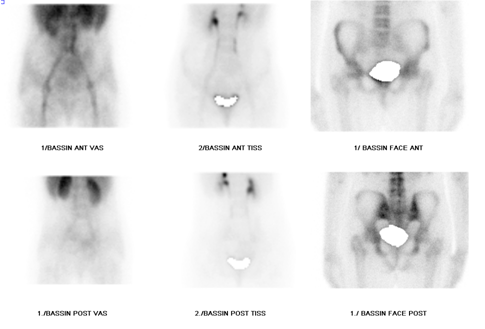

The incidences carried out during the flow phase and the blood pool phase did not demonstrate a clearly individualizable perfusion or uptake anomaly regarding the two hips (Figure 1). At the delayed phase, a unilateral hyperfixation was objectified to the left femoral head, the complement of which by SPECT - CT allowed an analysis of the sphericity of the femoral head with the possibility of staging of osteonecrosis in stage II according to the classification of Arlet and Ficat (Figure 2). The patient subsequently underwent a total left hip arthroplasty with favorable outcome.

Figure 2 SPECT-CT imaging showing a unilateral hyperfixation of the left femoral head corresponding to a heterogeneous density respecting the contours and the joint space in favor of osteonecrosis of the femoral head in stage II of Arlet and Ficat.